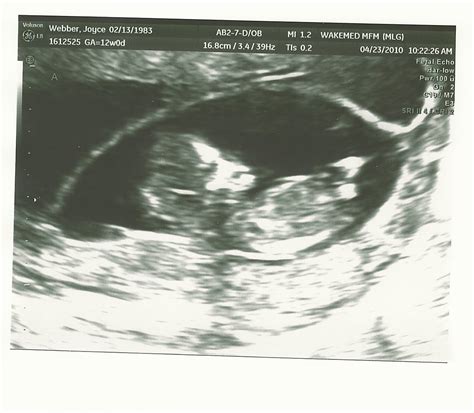

Pregnancy is an exciting journey filled with milestones, and one of the most anticipated is the 12 week ultrasound. This crucial scan provides valuable insights into the development of the fetus and the overall health of the pregnancy. Understanding what to expect during this ultrasound can help alleviate anxiety and prepare expectant parents for the experience.

A 12 week ultrasound, also known as the nuchal translucency scan, is typically performed between 10 weeks and 13 weeks and 6 days of pregnancy. This scan is essential for several reasons, including assessing the baby’s development, checking for any potential abnormalities, and measuring the nuchal translucency, which is the fluid-filled space at the back of the baby’s neck. This measurement is crucial for screening for chromosomal abnormalities such as Down syndrome.

The 12 week ultrasound is usually performed transabdominally, meaning the ultrasound probe is moved over the abdomen. In some cases, a transvaginal ultrasound may be used for better visualization, especially if the baby is positioned deeply in the pelvis.

During the procedure, the technician will apply a gel to the abdomen to enhance the transmission of sound waves. The probe will then be moved over the abdomen to capture images of the fetus. The entire process typically takes about 20-30 minutes.

During the 12 week ultrasound, several key measurements and assessments are made:

• Crown-Rump Length (CRL): This measurement from the top of the baby’s head to the bottom of the spine helps determine the gestational age and due date.

• Nuchal Translucency (NT): The thickness of the fluid-filled space at the back of the baby’s neck is measured. This measurement, along with maternal age and blood tests, helps screen for chromosomal abnormalities.

• Heartbeat: The baby’s heartbeat is checked to ensure it is within the normal range.

• Anatomy: The technician will look for the presence of the nasal bone, which is an important marker for Down syndrome. They will also check for the presence of both arms, legs, and the stomach bubble.